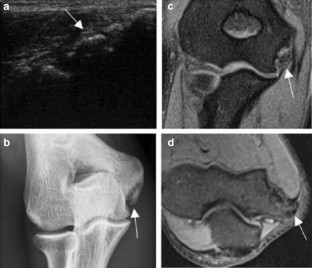

Fig. 1